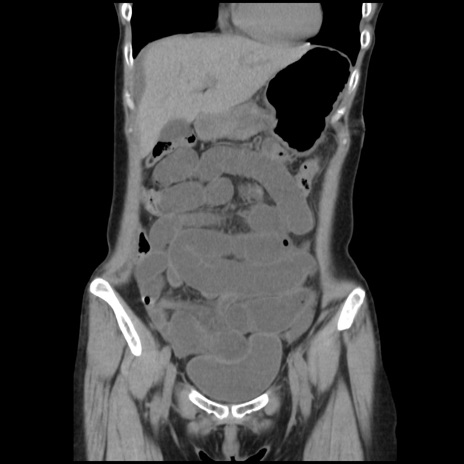

症例32(冠状断像)

【症例】40歳代 女性

【主訴】上腹部痛、嘔気・嘔吐

【現病歴】約9時間前頃から急に上腹部痛、嘔気、嘔吐が出現。改善しないため救急要請。

【既往歴】子宮頚癌(広汎子宮全摘術、放射線療法)、腸閉塞

【身体所見】腹部:平坦、軟、腸雑音亢進、上腹部を中心に腹部全体に圧痛あり。

【データ】WBC 8400、CRP 0.03